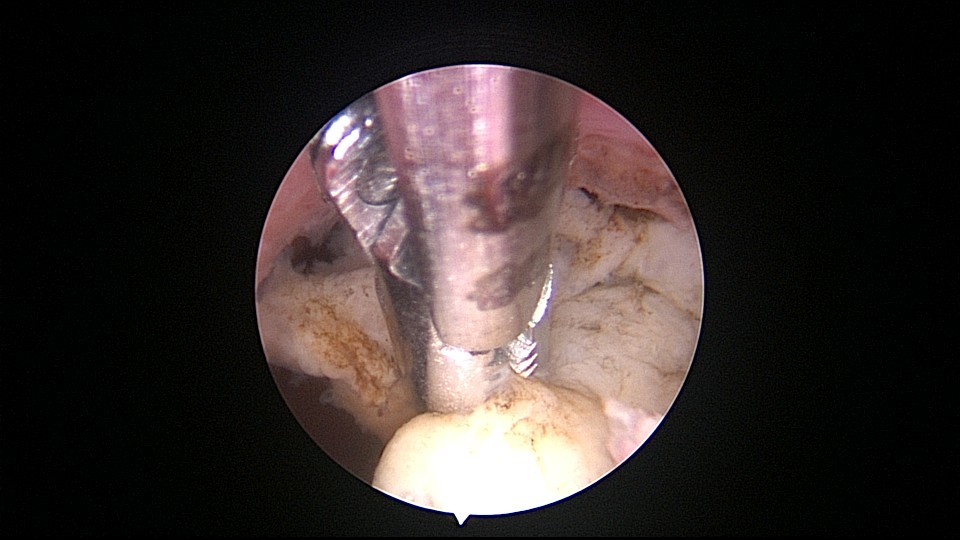

患者69岁,G2P1,顺产1次。产后曾安环1次,后自然脱落,再次安环距今40年,绝经20+年。外院取环失败(没有进入宫腔)。B超子宫后位,宫内O型环距宫底0.3cm,宫腔积液(按以往经验,考虑宫腔积脓),另见宫内稍强回声1.1cm*0.8cm。子宫极度后倾后屈位,宫颈管狭小坚硬,扩张困难,宫腔镜难以进入。宫腔镜直视下充盈膀胱,B超监护下异物钳指示宫腔方向,宫腔镜艰难进入宫腔,见灰白色脓液涌出,O型环位置正常,宫腔后壁占位包块位于节育环圈内,约1.5cm*1.5cm*1cm,异物钳顺利取出节育环。单极电针切除占位包块,但包块直径大于宫颈内口直径,异物钳多次尝试取出,均失败,不得已用单极电针切开宫颈内口左侧狭窄处,异物钳缓慢牵拉取出标本,膨宫液冲洗宫腔脓液,宫腔无其他异常。包块病检为内膜息肉。